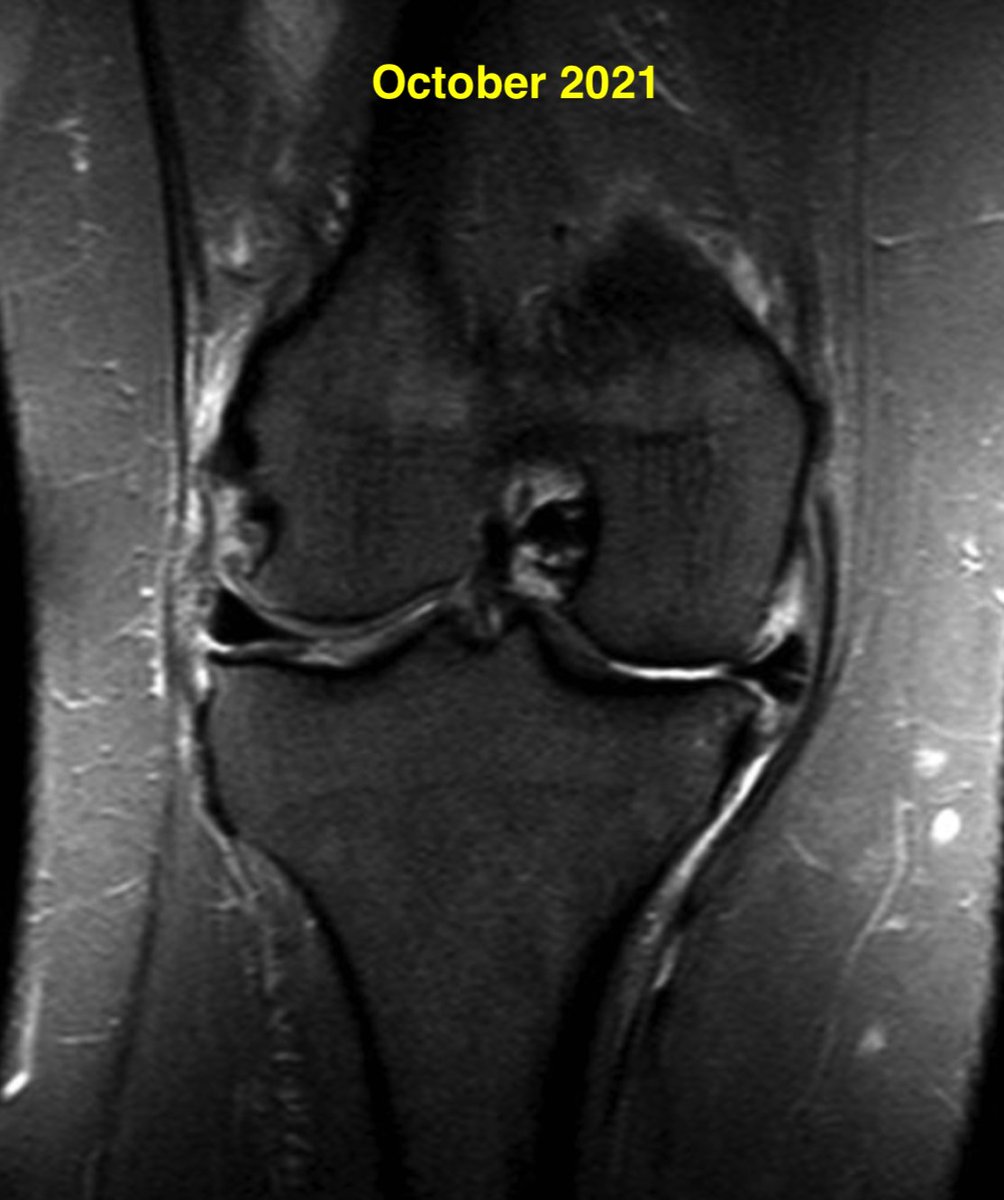

Meniscus root tears are important to recognize and address. Unfortunately, the natural history of a medial meniscus root tear can be seen in this patient when left untreated, with rapid progression of medial arthritis. #savethemeniscus #orthotwitter

Daniel Liechti, MD tweet mediaDaniel Liechti, MD tweet mediaDaniel Liechti, MD tweet mediaDaniel Liechti, MD tweet media